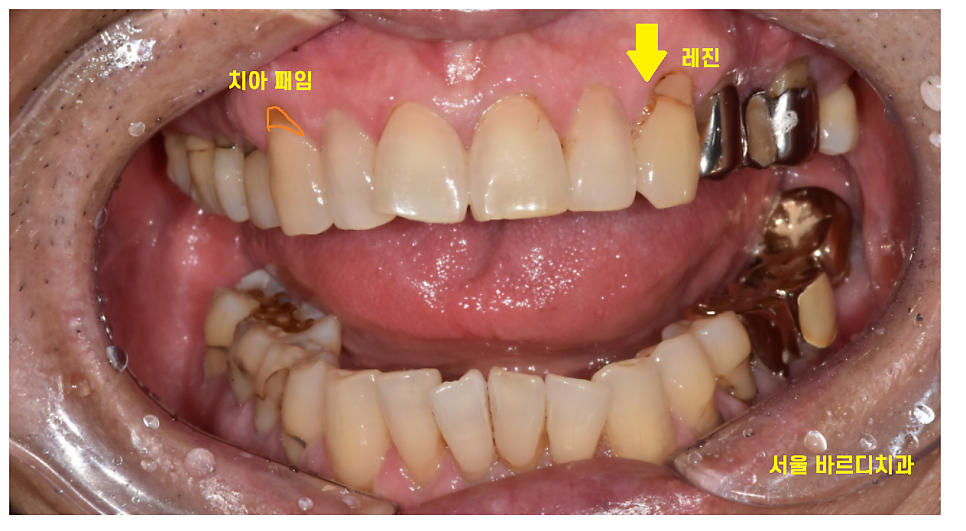

지난 시간 레진 재료를 이용하여

앞니 공간을 메운 환자분을 소개해드렸습니다.

레진

충치치료의 가장 간단한 치료방법인데요.

치료 부위도 다양하게 활용할 수 있습니다.

치아 목 부위가 파였을 때

떼우기도 하고

씹는면에 생긴 얕은 충치를 떼우는 재료기도 합니다.

지난 시간 소개해드린

앞니 공간을 메꿀때도 활용되기도 하고요.

다양한 부위에 광범위하게 사용되는 레진

치아 색깔과 유사하여 티가 나지 않고

강도가 강하여

치과 재료 중에서 가장 기본이 되는 재료입니다.